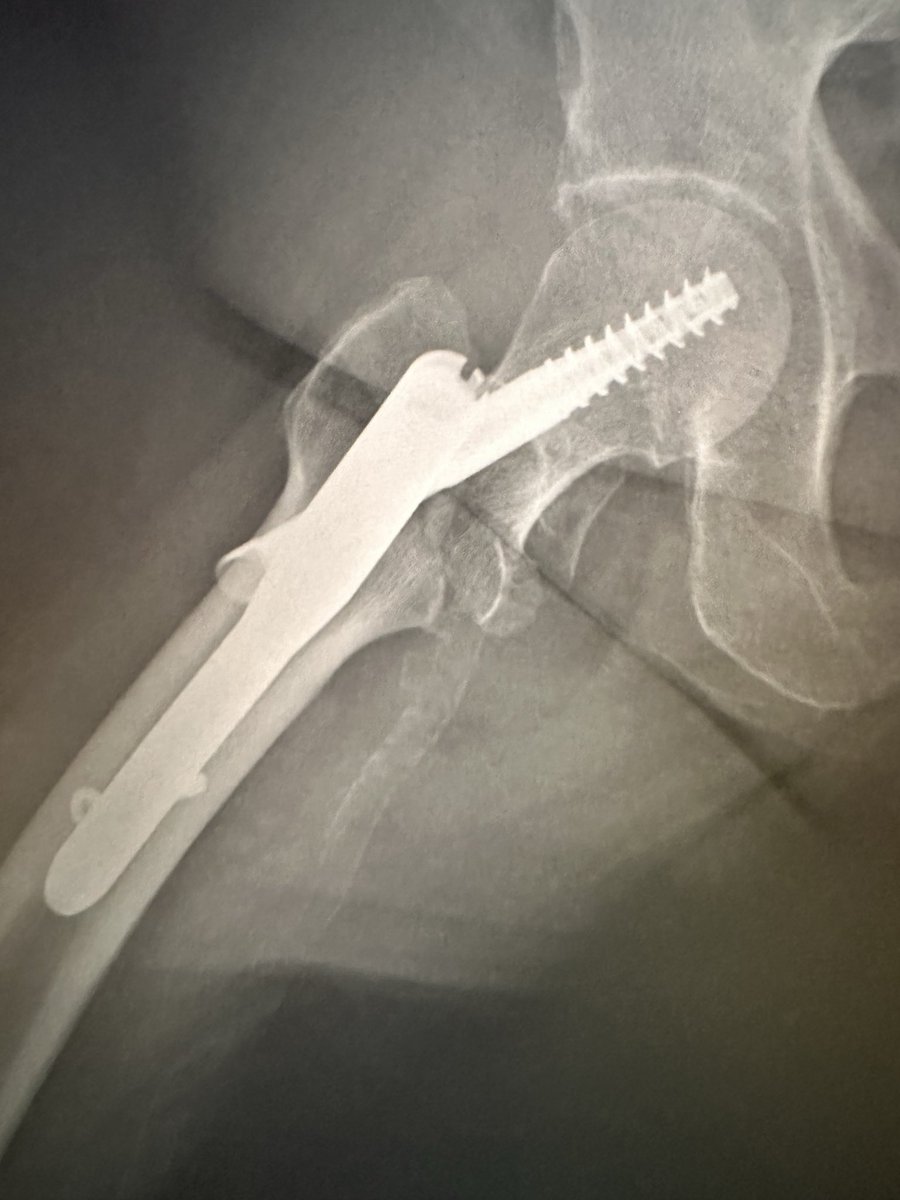

Here is a new case by Dr. Jonathan Yerasimides and Louisville Institute of Orthopaedics.

GROIN PAIN AND LEG LENGTH DISCREPANCY S/P THA IN 65F

This case will be discussed at the Anterior Hip Foundation (@AAHips) 2026 "Consensus & Controversy" in Nashville, Tennessee, June 5-6, 2026.

How would you manage this #orthotwitter?

Vote on this case for CME: orthobullets.tiny.us/yudd4as3

@northwoods1980 Le faltó tracción a la hora de colocar el tornillo.